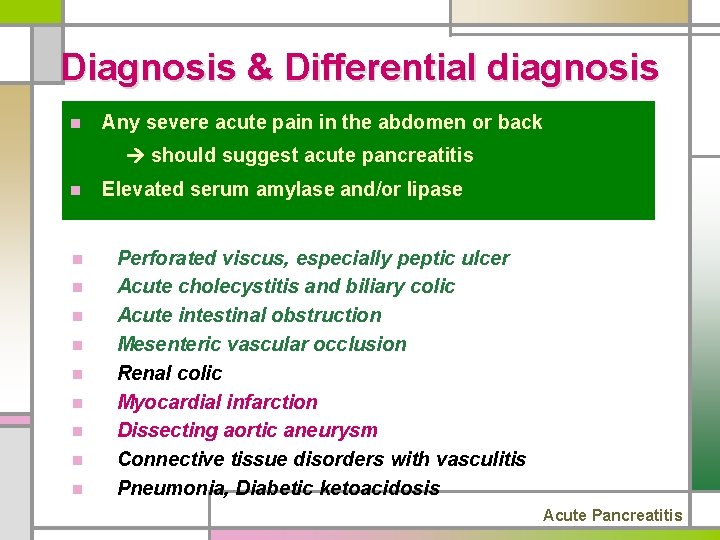

Diagnosis & Differential diagnosis n Any severe acute pain in the abdomen or back should suggest acute pancreatitis n n n n n Elevated serum amylase and/or lipase Perforated viscus, especially peptic ulcer Acute cholecystitis and biliary colic Acute intestinal obstruction Mesenteric vascular occlusion Renal colic Myocardial infarction Dissecting aortic aneurysm Connective tissue disorders with vasculitis Pneumonia, Diabetic ketoacidosis Acute Pancreatitis